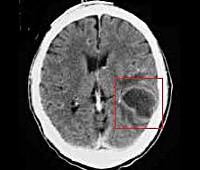

• Абсцесс головного мозга, мозжечка. Патологические полости, ограниченные пиогенной мембраной и заполненные гнойными массами. Типичное расположение при отогенном происхождении - височная доля, мозжечок.

• КТ или МРТ головного мозга. Исследования дают возможность четко визуализировать локализацию абсцессов или очагового энцефалита, определить их размеры, выявить перифокальный отек, дислокацию и деформацию желудочков мозга. Контрастные методики показаны при подозрении на тромбоз кавернозного или сигмовидного синуса.